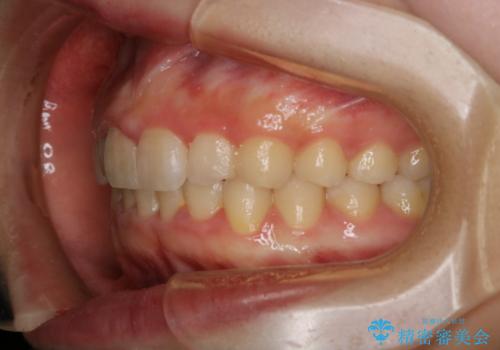

前歯のがたつきとディープバイト:インビザライン治療

- 前歯のがたつきと、噛み合わせが深いことを気にされてご相談にいらした方です。

インビザラインにて治療を行いました。

一般的に、歯冠(歯の長さ)が短い方はインビザライン治療に時間がかかりやすい傾向にあります。

歯の移動量に対して大きなブラックトライアングルもできることなく綺麗に並べることができ、大変喜んでいただけました。